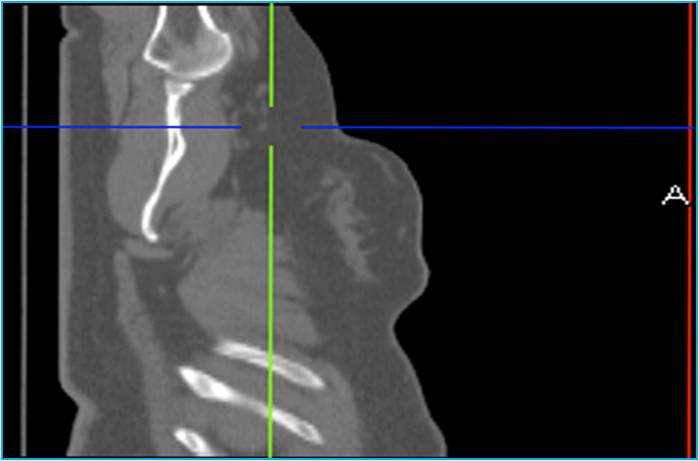

Чем изображения радионуклидной диагностики отличаются от изображений лучевой диагностики? Лучевая диагностика — это визуализация изменений рентгеноморфологии, что больше относится к морфологической структуре или анатомии. С помощью радионуклидной диагностики специалисты видят физиологические или патофизиологические изменения, которые происходят в организме на клеточном уровне.

Рис. 1. Лучевая диагностика. Визуализация изменений морфологической структуры или анатомии